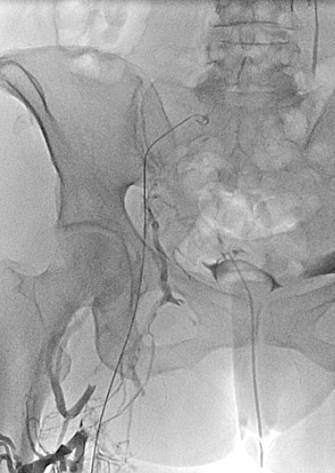

Paciente de sexo femenino de 35 años de edad con sarcoma endometrial metastásico y la pierna izquierda muy hinchada.

Pierna izquierda muy hinchada, a pesar de llevar medias de compresión de clase 2 hasta la altura del muslo. Obsérvese la bolsa del catéter de drenaje para nefrostomía.

Venograma de la pierna izquierda donde se muestra un trombo oclusivo en las venas profundas más visualizadas.

Venograma en posición de decúbito prono de la rama ilíaca izquierda que indica una estenosis causada por el tumor que comprime la uretra y la vena ilíaca externa izquierda.

Eliminación razonable del trombo en las venas ilíacas tras una sola pasada del catéter DVX de AngioJet (25 mg de tPA en 250 cc de solución salina normal).

Venograma final tras la aspiración con catéter grande y tratamiento de la estenosis subyacente (debido a la compresión extrínseca del tumor) con un stent de 16 mm con el balón inflado a 12 mm.

Tiempo total: <90 minutos. Flujo interno perfecto de la parte posterior de la rodilla a la vena cava inferior (VCI).

Tras cuatro meses y medio; capacidad para caminar normal, sin hinchazón.

Gerard O’Sullivan, University College Hospital, Galway, Irlanda (2009)